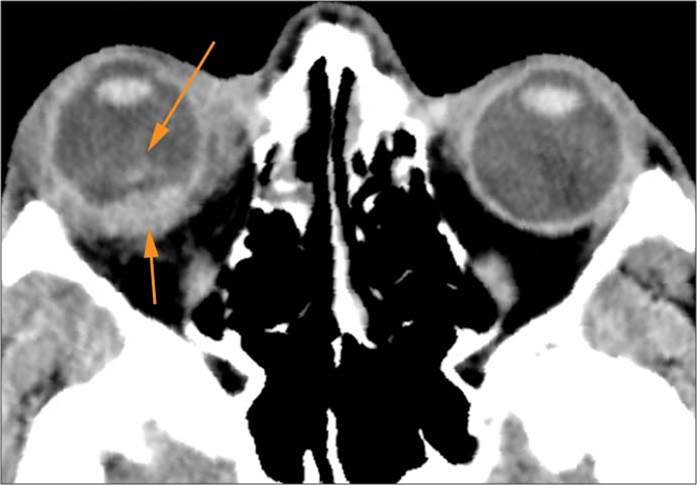

The circumferential extraconal and the intraconal orbital fat are infiltrated. [Yes/No]

There is evidence of herniated intra-orbital fat. [Yes/No]

Proptosis is present. [Yes/No]

There is evident subretinal, subchoroidal or intravitreous hemorrhage. [Yes/No]